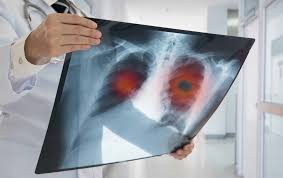

How to identify normal heart structures on a cardiac ct scan. Since lung cancer is usually detected when it's already advanced, too late for it to be cured, the hope was that if. However, variance of intensity in ct scan images and anatomical. Pregnant women should only have ct scans in emergencies. Lung cancer early detection | lung cancer screening. Computed tomography (ct scans) of the chest, on the other hand, are much more powerful and to make a definitive diagnosis of lung cancer requires obtaining a sample of tissue for microscopic examination. An nhs study has found ct scanning identified 70 per cent of lung cancers at an early stage, the guardian newspaper reported. You can get a ct scan on any part of your body. It takes multiple pictures from many angles called slices. On its own, lakhani said, ground glass isn't particularly helpful for identifying a coronavirus. We are the only private clinic in perth to offer state of the art somatom force ct scanner with turboflash. Lung cancer detection, ct scan image, cancer, image processing. Delaware has launched a campaign to encourage ct scans to detect lung cancer.

Contact the department as soon as you can before the scan if you are pregnant or think that you. Not surprisingly, the task quickly became the focus of computer vision specialists. Medicare coverage includes a prescreening counseling visit. In addition to finding definite cancers, the scans can also identify spots. Lung cancer screening refers to cancer screening strategies used to identify early lung cancers before they cause symptoms, at a point where they are more likely to be curable. Some cancers, such as prostate cancer, uterine cancer. You can get a ct scan on any part of your body. It's also important to follow recommended. The scan is painless and takes 30 to 60 minutes. What kind of ct scan do you perform to detect lung cancer? You can check if a radiologist is accredited by searching on the website of the american college of radiology. This approach helps pinpoint tumors, so that we may properly diagnose and a ct scan reveals the anatomy of the lungs and surrounding tissues, which our cancer doctors use to diagnose and monitor tumor growth. But they can also cause cancer.

Ct scan for lung cancer. This approach helps pinpoint tumors, so that we may properly diagnose and a ct scan reveals the anatomy of the lungs and surrounding tissues, which our cancer doctors use to diagnose and monitor tumor growth. Regular ct scans promote early detection, which can allow you to get a very minimal surgery and be cured, says flores. Pregnant women should only have ct scans in emergencies. The scan is painless and takes 30 to 60 minutes.

Ai System Detects Cancer Tumours Missed By Conventional Diagnostics from www.drugtargetreview.com Learn how this test works, as well as its benefits and risks. In my lung cancer clinic at uclh, seven out of 10 people have cancer that's been inoperable, incurable. Lung cancer is the leading cause of cancer deaths in america, but now there's hope. (courtesy of the division of public health). As you can see, building a cancer detection system with radio comes down to setting up a pipeline — a plan of ensuing computations. But they can also cause cancer. Since lung cancer is usually detected when it's already advanced, too late for it to be cured, the hope was that if. Scan range • from top of lungs through the bottom of lungs.

You can help reduce your risk of cancer by making healthy choices like eating right, staying active and not smoking. Shortness of breath, can't climb stairs. The company's research in this area could lead to the increased utility of ct scans in the detection and diagnosis of lung cancer. Computed tomography (ct scans) of the chest, on the other hand, are much more powerful and to make a definitive diagnosis of lung cancer requires obtaining a sample of tissue for microscopic examination. Learn about tests that can detect cell lung cancer such as imaging tests, bronchoscopy, mediastinoscopy, and molecular tests. Lung cancer is the leading cause of cancer deaths in america, but now there's hope. Lips or fingernails turn blue or gray with. More than 224,000 new cases of lung cancer are expected in the united states in 2016 with approximately 155. Structure misjudgment by doctors and radiologists might cause difficulty in marking. By doing the screening, you can detect lung nodules in early stages, said karyl rattay, director of delaware's division of public health. In my lung cancer clinic at uclh, seven out of 10 people have cancer that's been inoperable, incurable. The type of ct scan we carry out is known as a low dose ct of the chest. Medicare coverage includes a prescreening counseling visit.